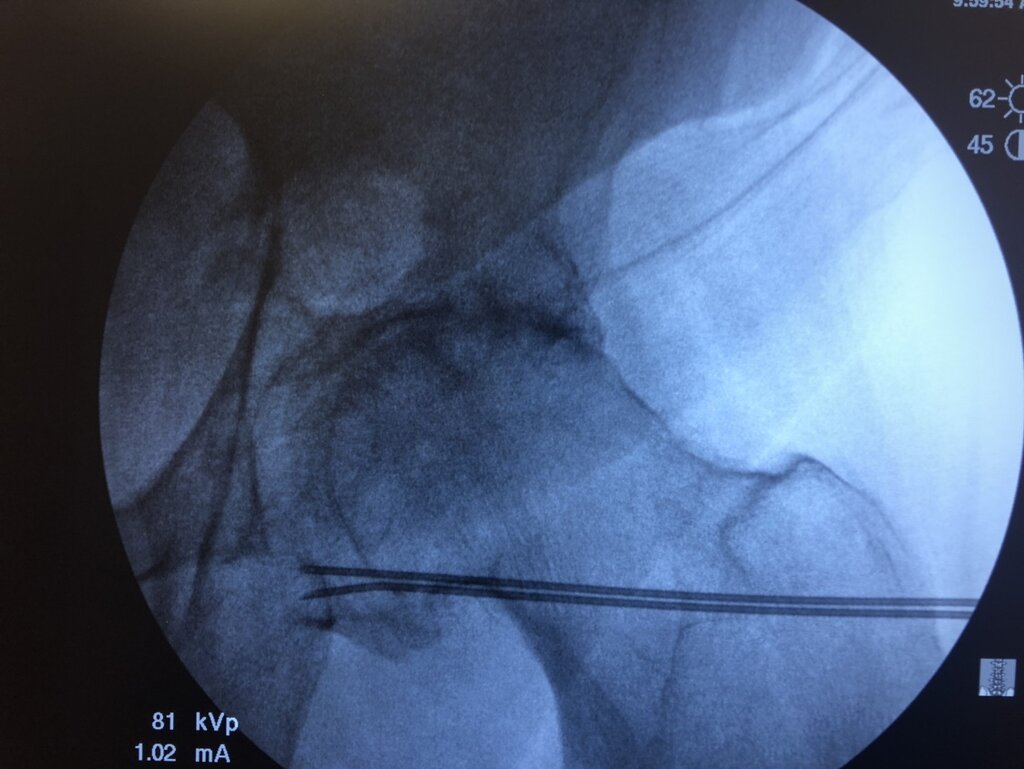

IMG_1501.jpg

IMG_1503.jpg

IMG_1502.jpg

Someone tell me what I did wrong. I’m not sure if this helped the poor guy.

This looks like VERY nice needle placement.

Remember these nerves are not in an anatomically consistent location such as with the medial branches...so can miss them even with great anatomic placement.

I was thinking his obturator placement was a little too lateral. I place them closer to the tear drop seen on the pelvis

Likewise, my femoral target is slightly superior to this placement, but I like these pics. In both cases, placement is on the expected nerve path (as best we can tell.) I adapted the placement from coolief "research." (I've posted their slides before)

Pmrmd, You didn't do anything wrong. That's a $#!+ Hip. Looks like you gave the patient a fair chance at benefit with the dull tool we are welding in 2019.

Up date: the guy with that hip RF is about 50% better. He thought the cracking sound was supposed to resolve too. Thanks for your input cowboy and swamprat

May I ask? Why are you insert two cannulas?